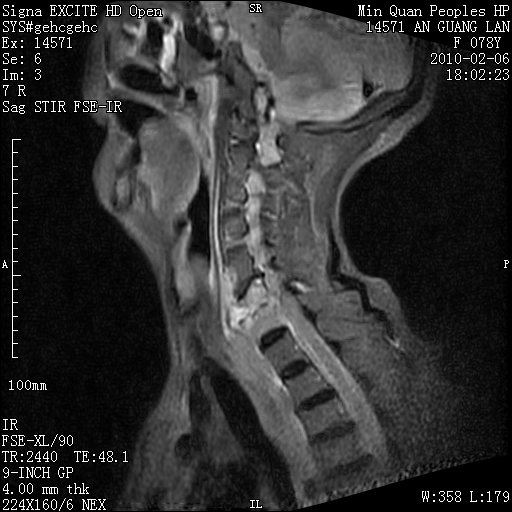

标题: MRI2763:C6、C7椎体病变性质?

f,78y,颈部与双上肢阵发性剧痛40余天。ct可见c6、c7椎体虫蚀样破坏,其间椎间隙变窄(没有图片资料可供上传)。